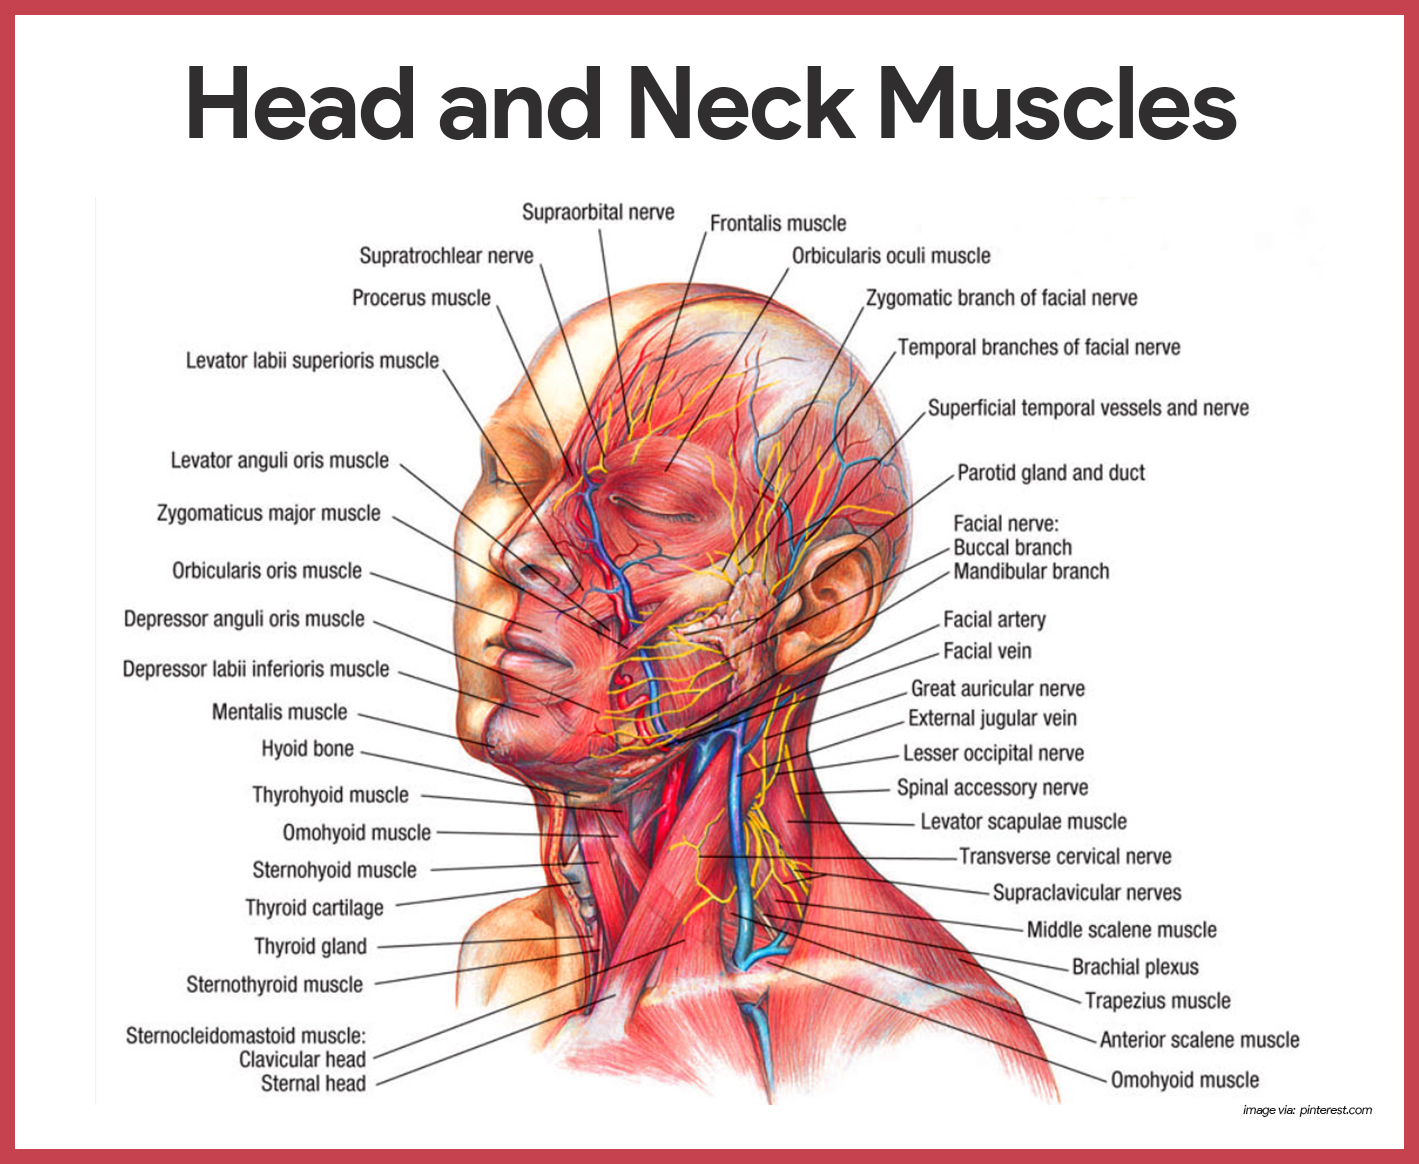

Neck Muscle Diagram Labeled Posted in diagrams scalenes muscles.

33 Label The Muscles Of The Head And Neck Labels Design Ideas 2020

Muscles of the neck / musculature of the cervical spine